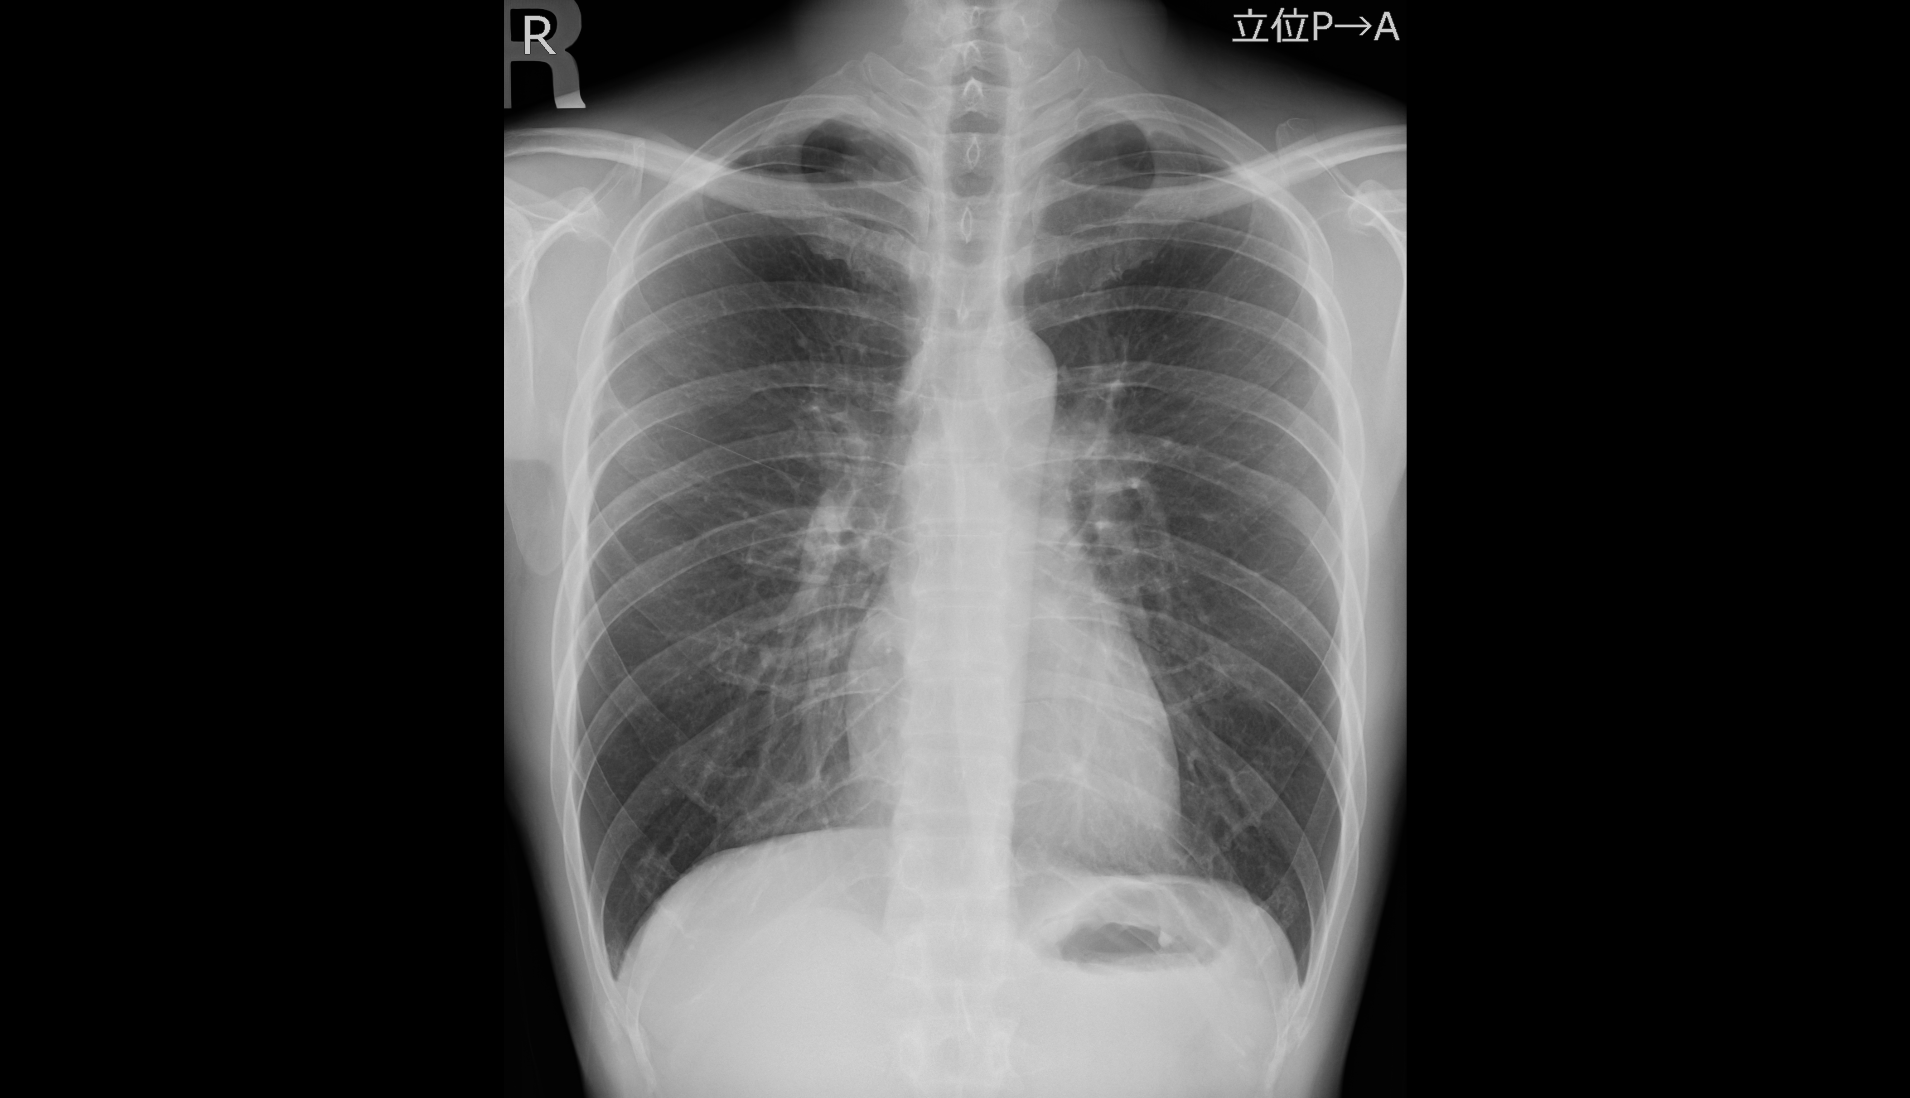

| 一般撮影 |

胸部や腹部、骨などの写真を撮影します。